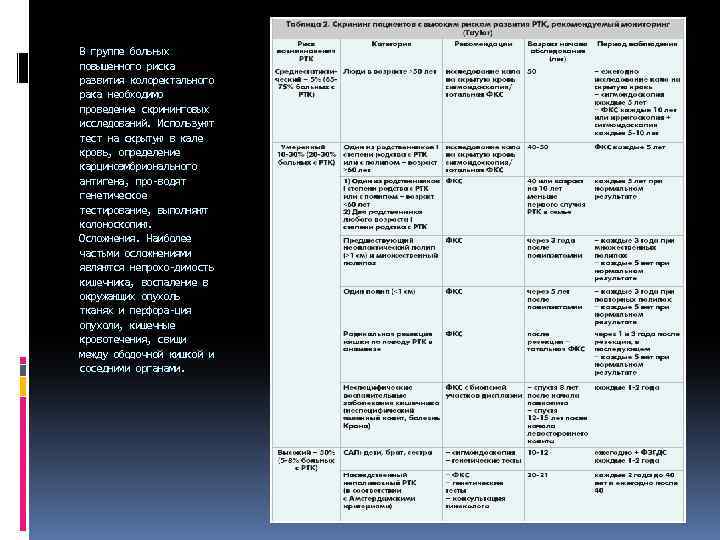

В группе больных повышенного риска развития колоректального рака необходимо проведение скрининговых исследований. Используют тест на скрытую в кале кровь, определение карциноэмбрионального антигена, про водят генетическое тестирование, выполняют колоноскопию. Осложнения. Наиболее частыми осложнениями являются непрохо димость кишечника, воспаление в окружающих опухоль тканях и перфора ция опухоли, кишечные кровотечения, свищи между ободочной кишкой и соседними органами.